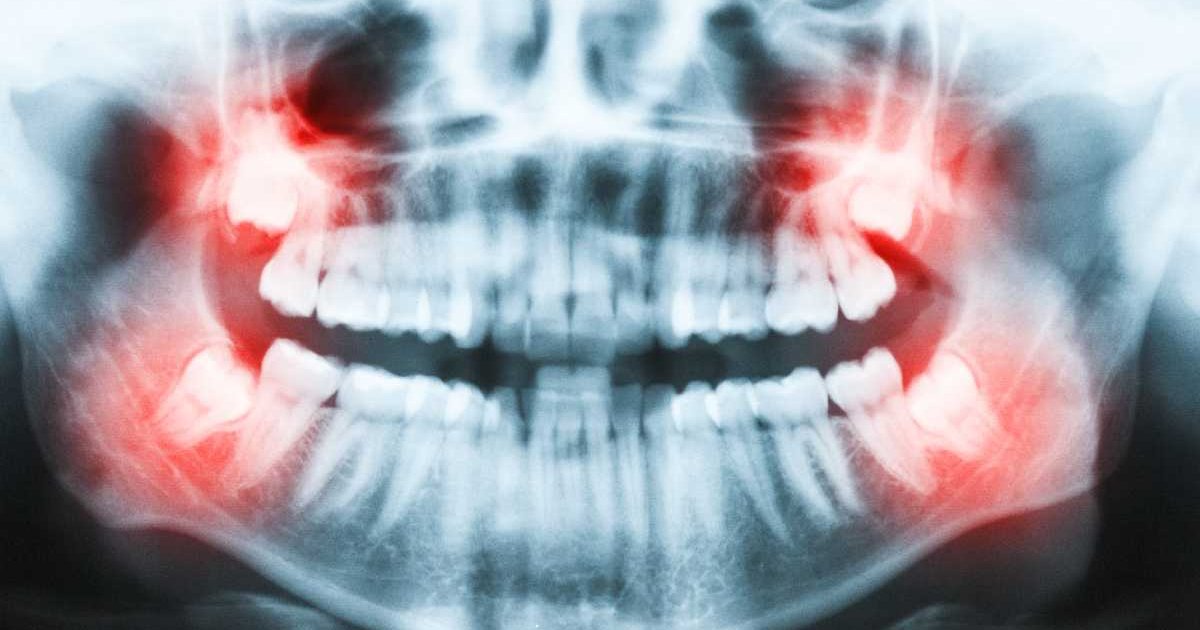

Zęby mądrości to ostatnie zęby trzonowe po obu stronach szczęk. Zazwyczaj pojawiają się one lub rosną jako ostatnie, zwykle w wieku od 16 do 20 roku życia. Ze względu na to, że.

W przypadku ósemek jest zupełnie inaczej. Pojawiać się one bowiem mogą dopiero po 17-18 roku życia. Zdecydowanie najczęściej wyrastają one u ludzi dopiero w.

Zęby mądrości to ostatnie i najdalej ku tyłowi położone zęby w łuku zębowym. Wyrzynają się u nas jako ostatnie wieku miedzy 18 a 22 rokiem życia, ale przeważnie.